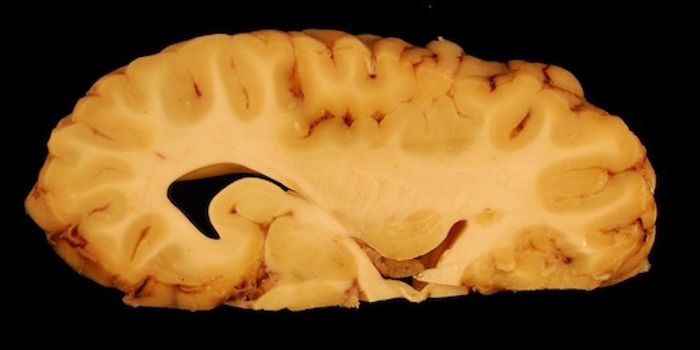

JUN 07, 2020Chemistry & PhysicsScientists from the University of Nottingham have published their most recent developments on a wearable 49 channel brai ...